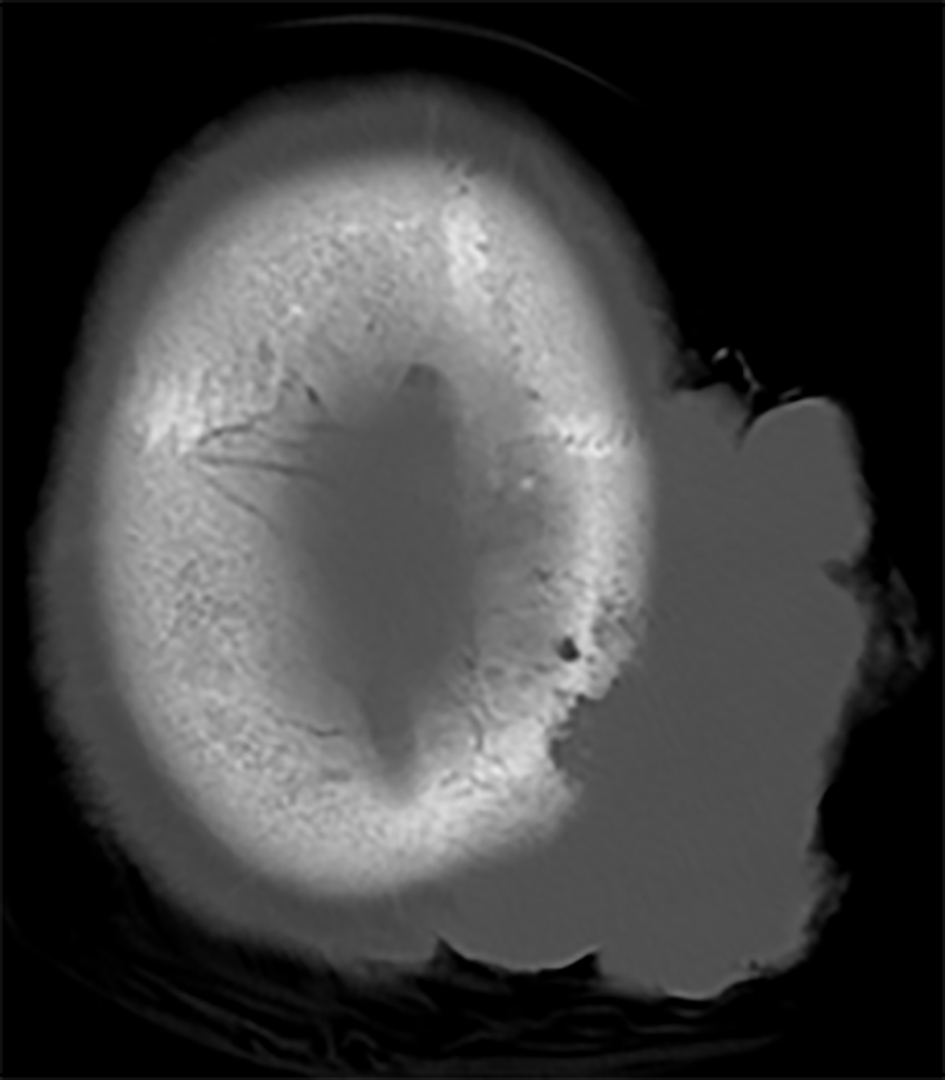

The patient however was readmitted a month later with hypotension and generalized weakness and signs and symptoms of sepsis. She was empirically started on broad spectrum antibiotics and hemodynamic support. Due to her intricate history and guarded prognosis infectious disease, medical oncology, hematology, and palliative medicine were involved in her care. This time the scalp lesion had grown in size. CT and visual inspection showed a tumor with dimensions more than 7 cm with a raised summit of approximately 1.5 cm that was invading the calvarium, as seen in Figure 3. The patient made a good recovery and is presently scheduled to undergo radiation of 5,000 - 6,000 cGy in 24 daily fractions. After informed discussion she was deemed unsuitable for aggressive chemotherapy.

![]() Click for large image | Figure 3. CT scan showing erosion of calvarium. |